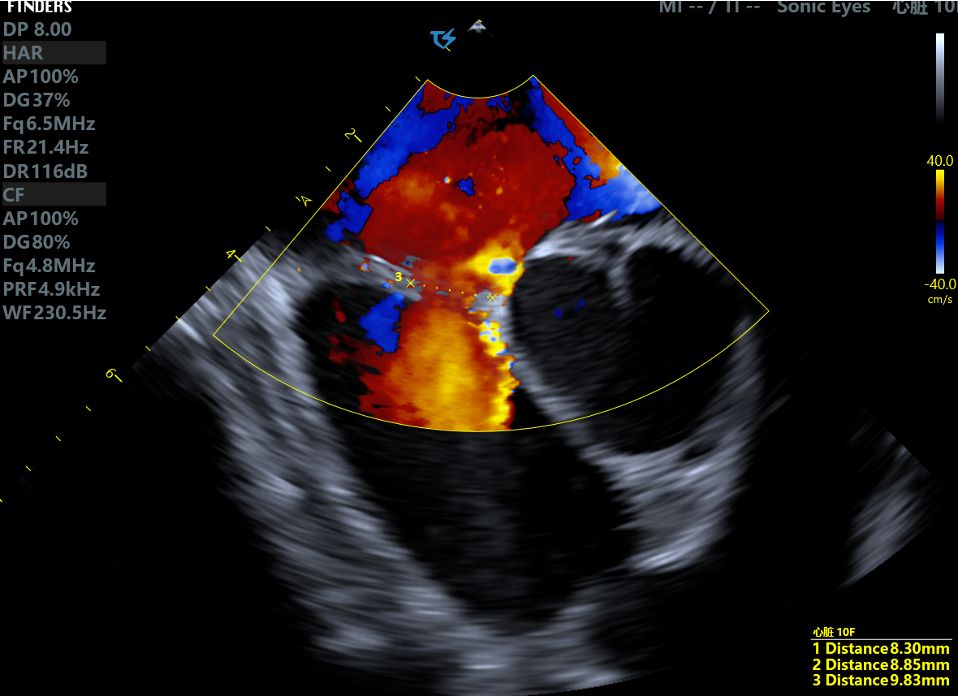

Clinical Strategy: During the procedure, intraoperative ICE ultrasound was used to reassess the defect size, measuring 9.83mm with a soft margin. Given the patient's young age and comprehensive evaluation, we selected the BDASD-I 16 (waist diameter is 16mm) biodegradable ASD occluder as the optimal solution for this case.